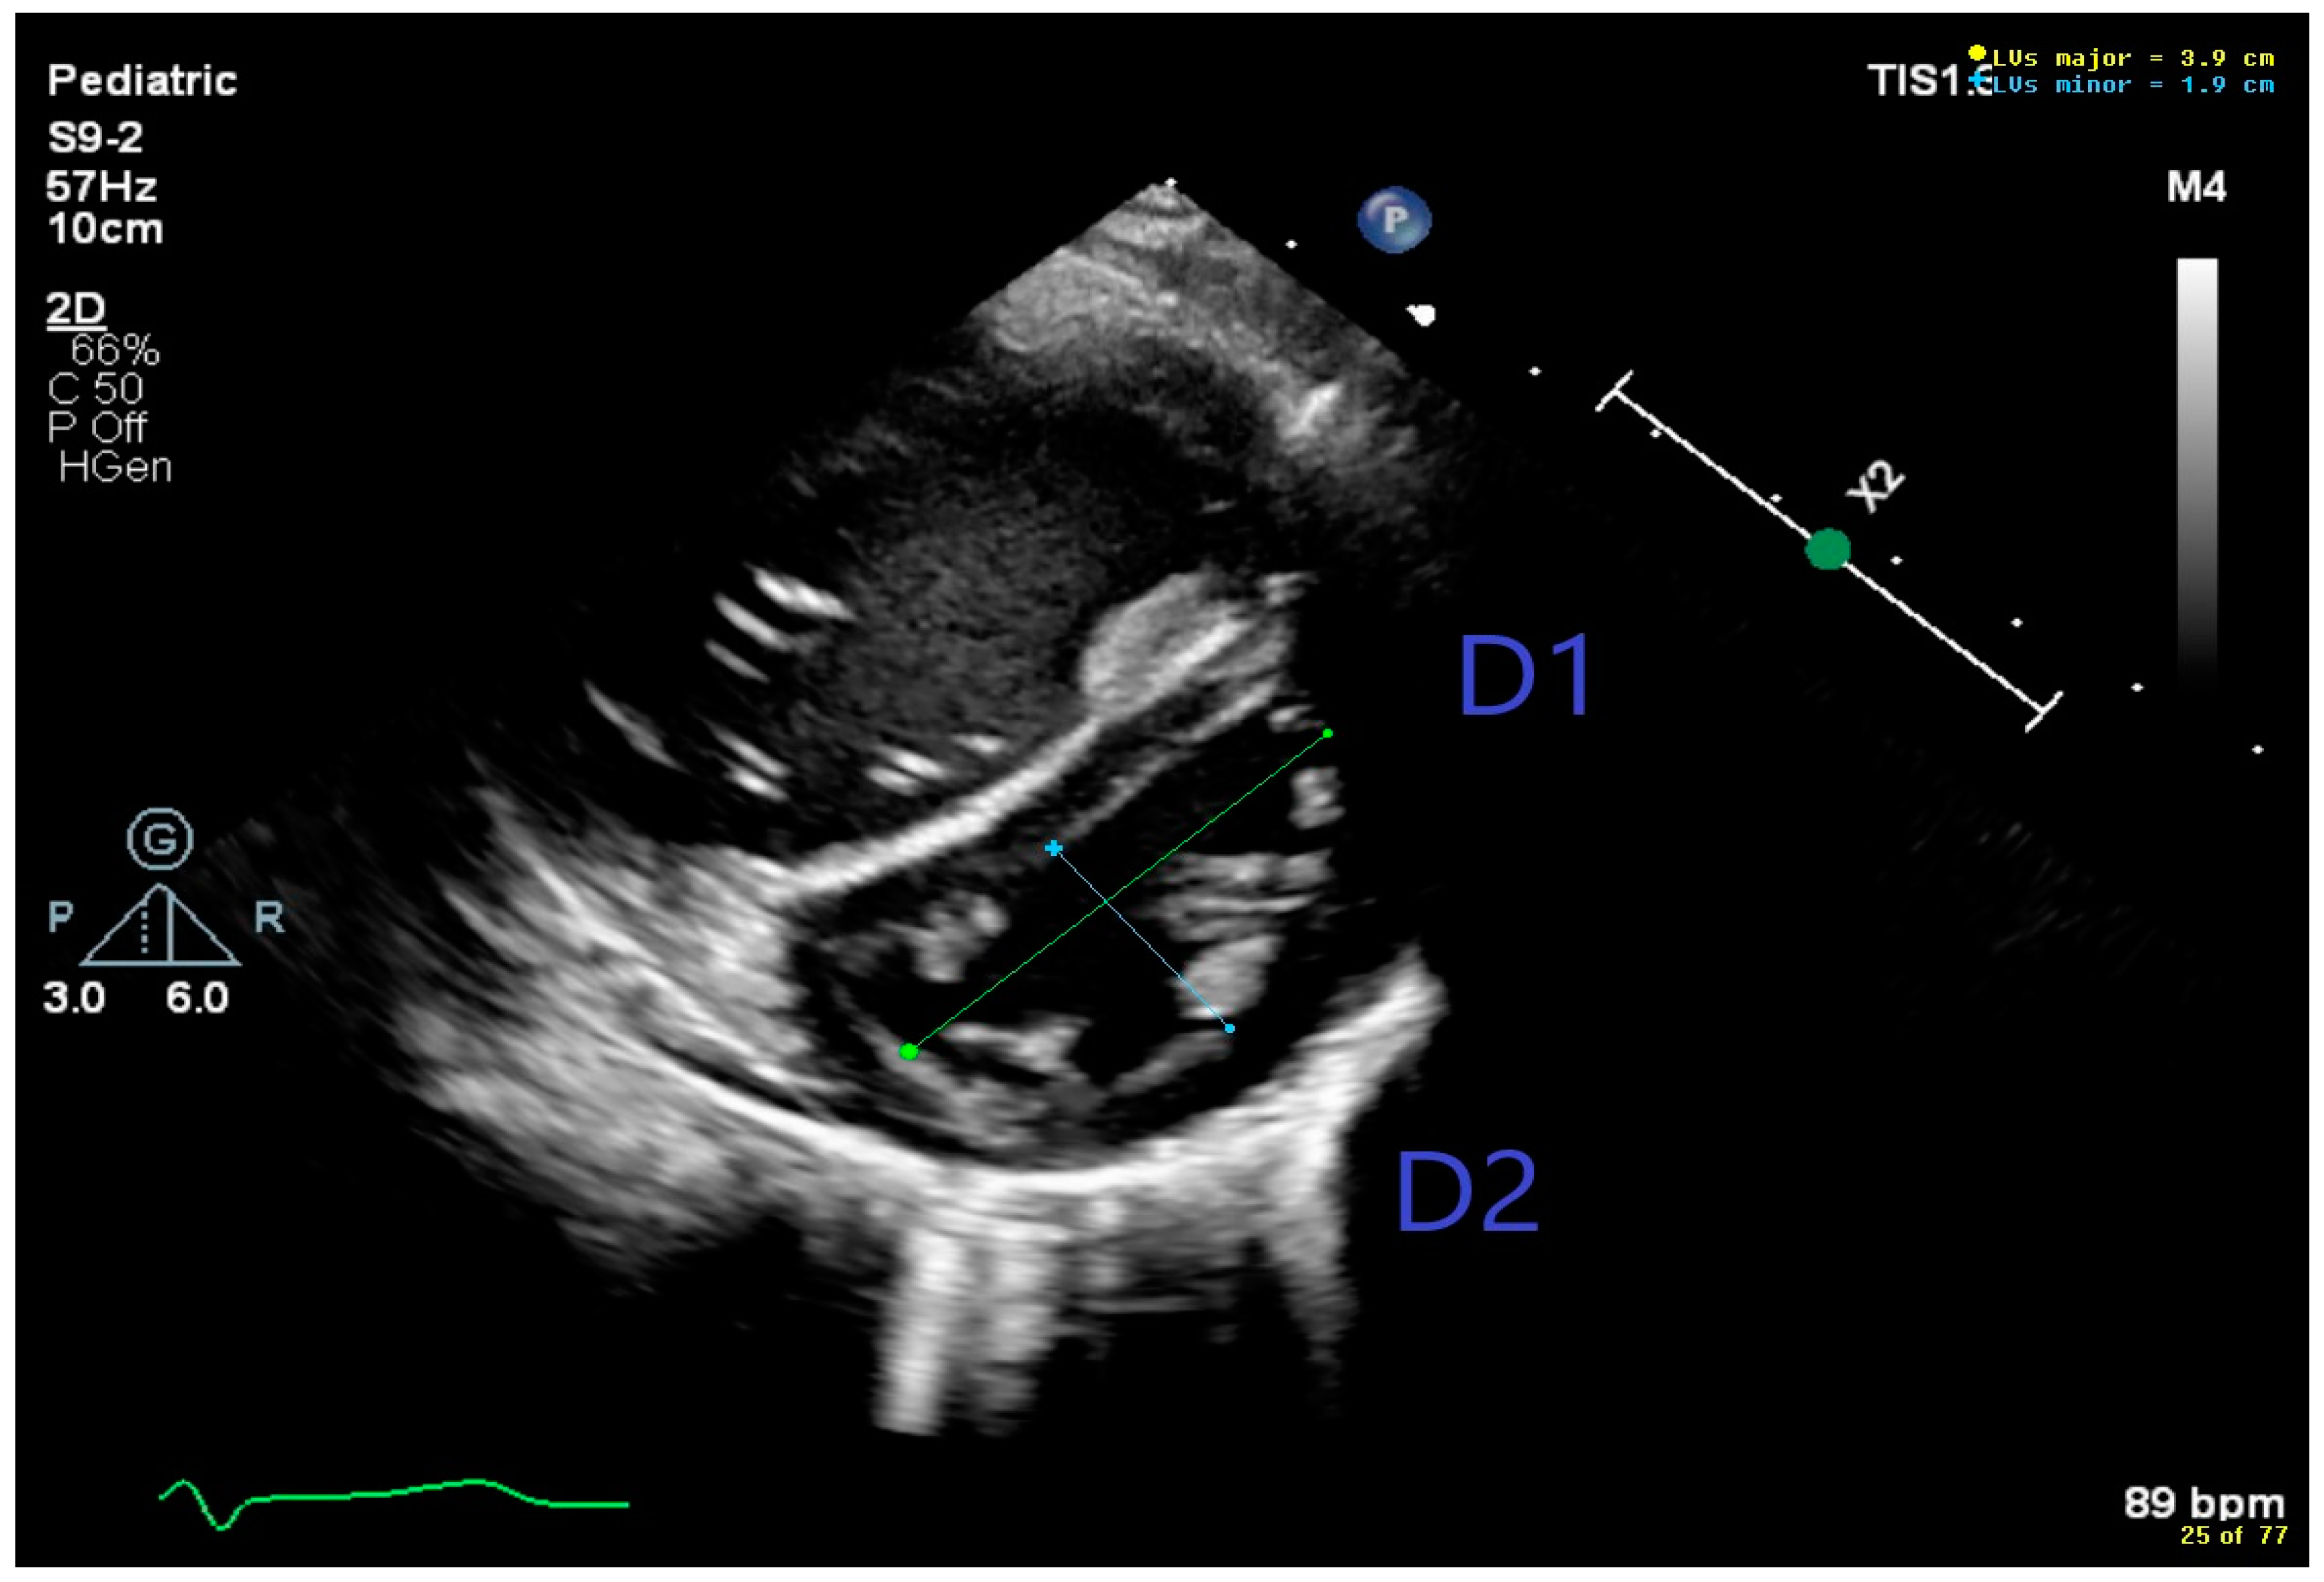

| LV sEI | Left Ventricular Systolic Eccentricity Index |

| TPV/RVET | Time To Peak Velocity/Right Ventricular Ejection Time Ratio |

| TAPSE | Tricuspid Annular Plane Systolic Excursion |